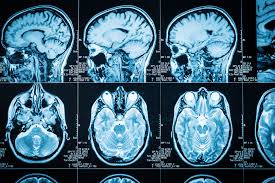

When x-rays passed into the body, it casts shadow of the bones. A doctor can read x-ray film and diagnose. But the body is also made up of soft tissues, nerves, muscles, fluids. They cannot be detected using x-rays. The 'magnetic resonance imaging (MRI) gives the full picture.

The amount of water content in a particular part of the body (say brain), energy released , value of returning to the normal state(protons). All these factors are interpreted by the computer software(MRI) and give us 2D or 3D image.